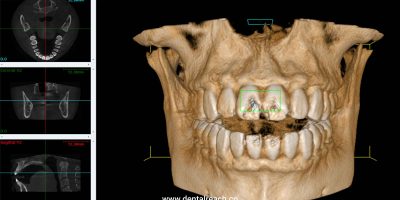

Cone Beam Computed Tomography in Endodontics

Cone Beam Computed Tomography (CBCT) including endodontics has become widely available and utilised in all aspects of ...